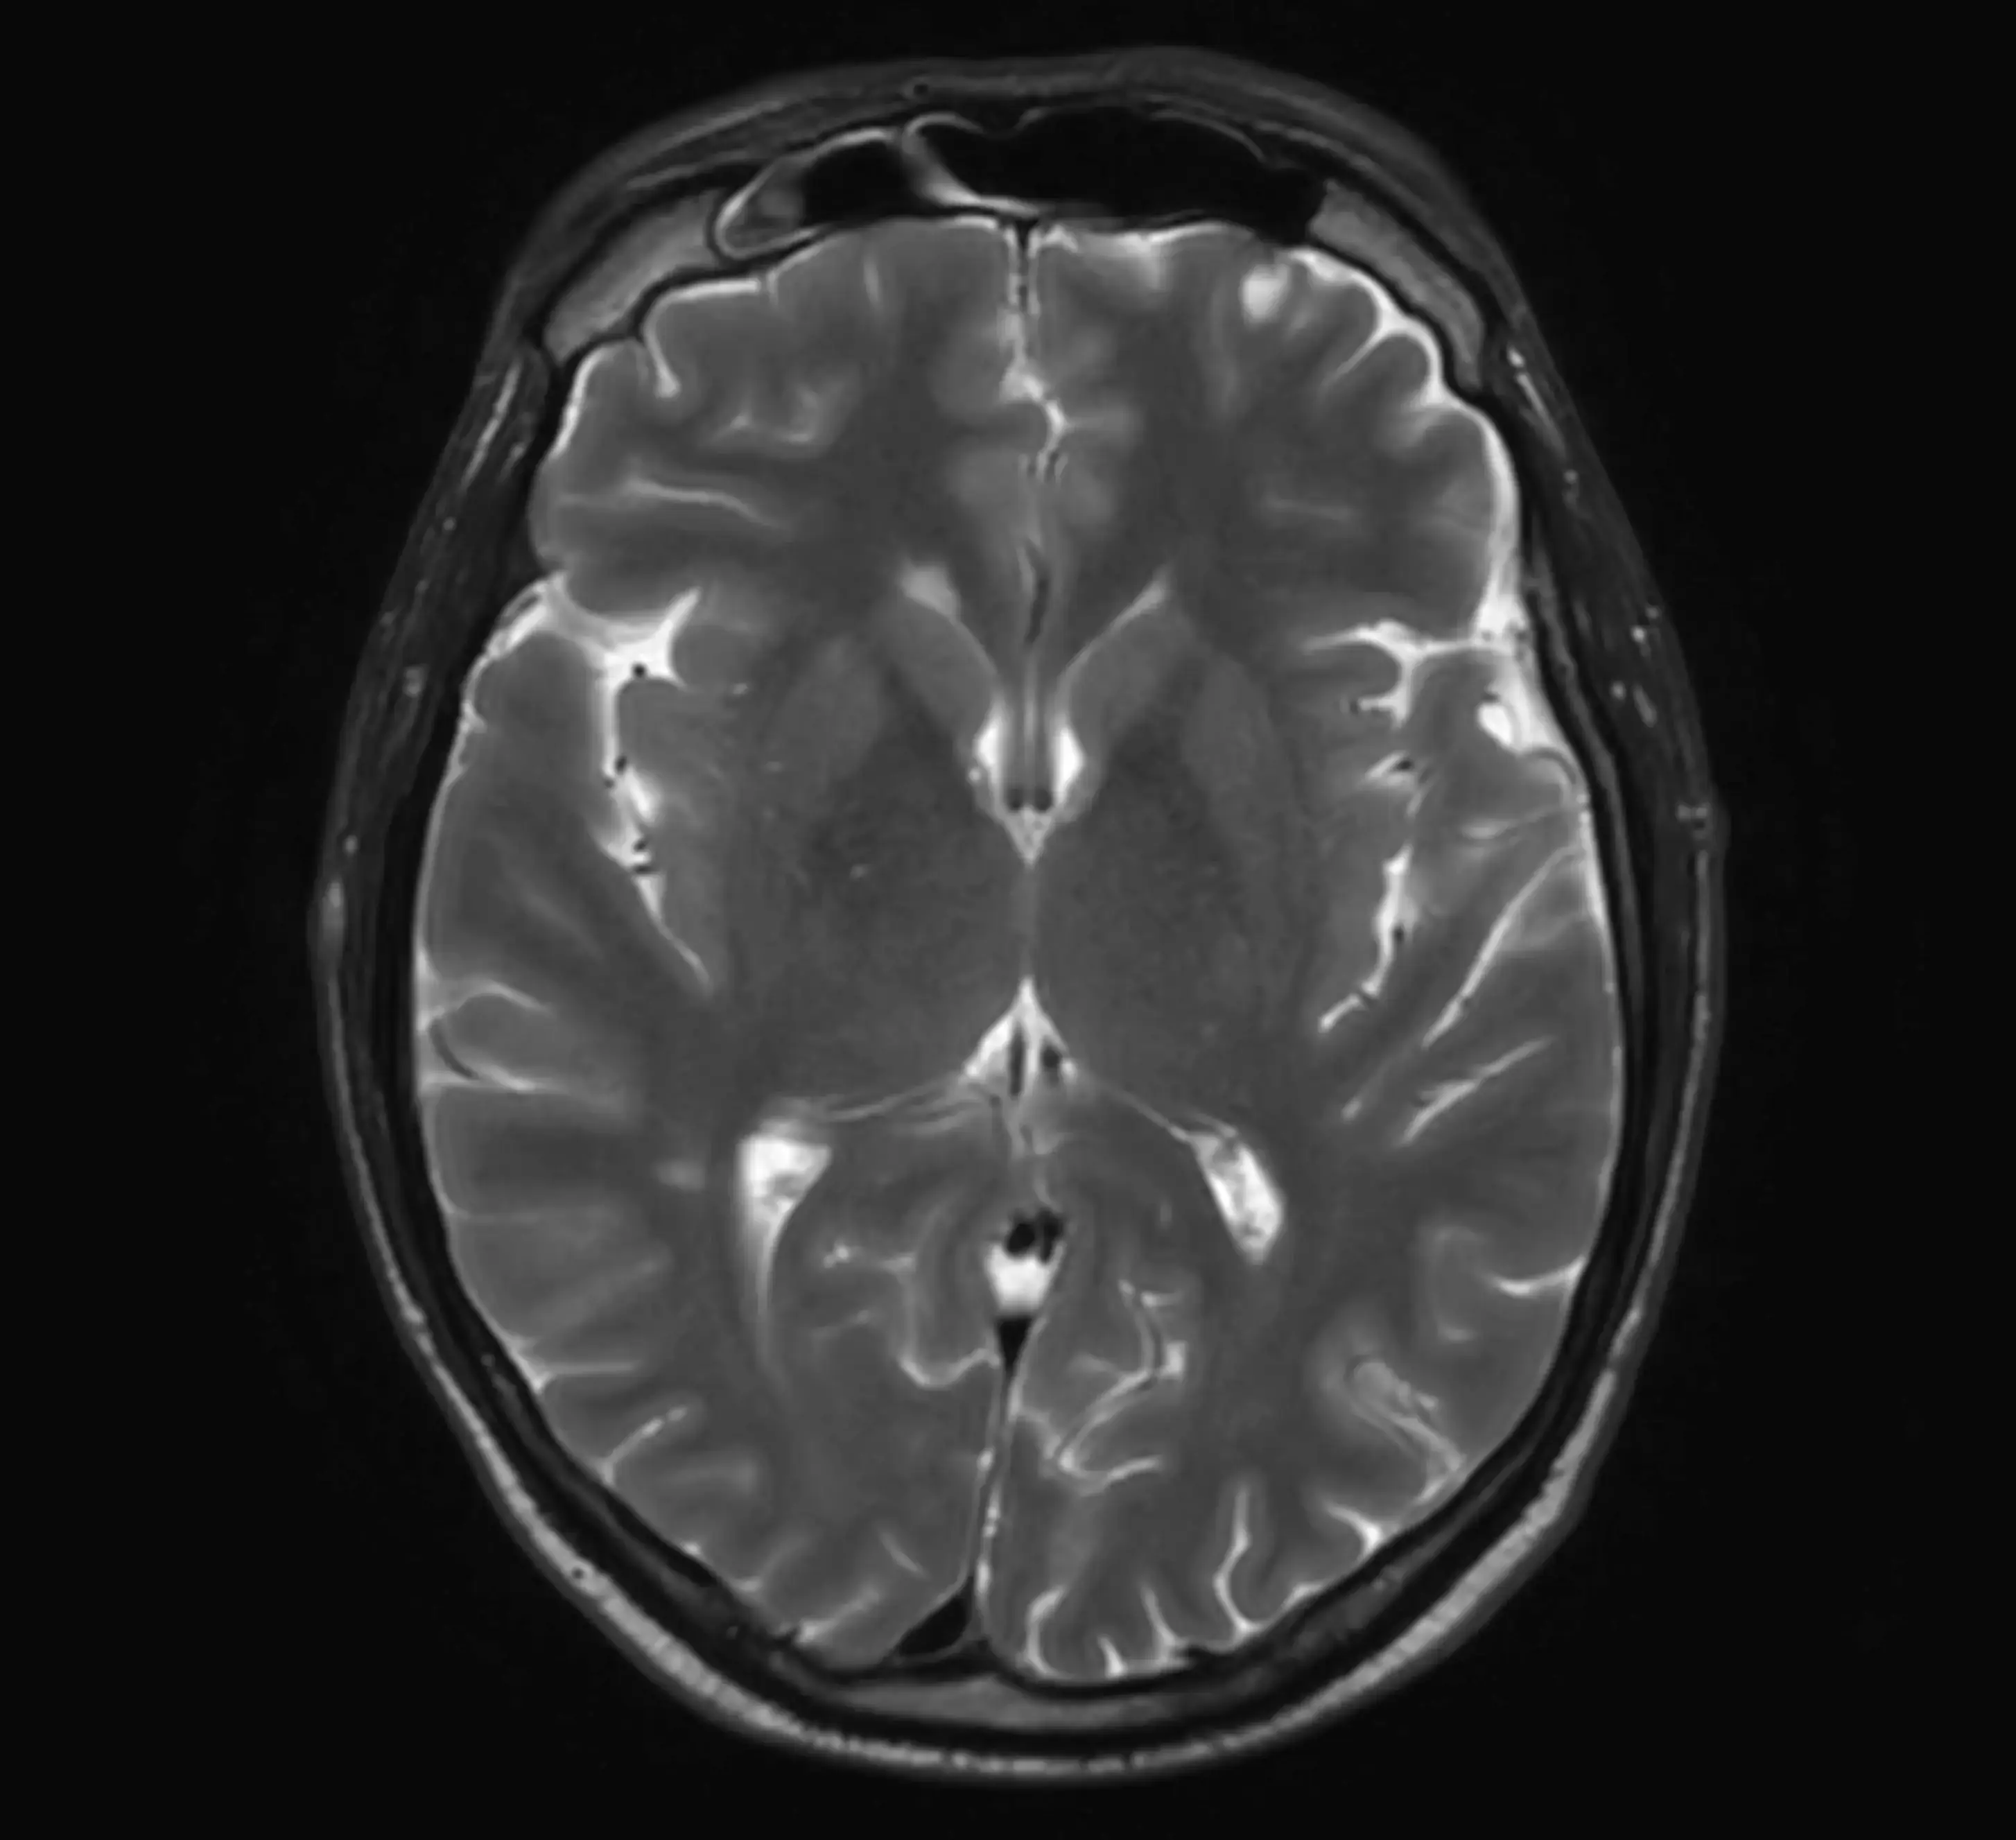

У центрі встановлено інноваційний МРТ Philips Ingenia 1.5T, оснащений технологіями штучного інтелекту (AI), що забезпечує високу точність зображень та дозволяє виявляти патології навіть на ранніх стадіях.

У центрі встановлено Philips Ingenia 1.5T — один із найсучасніших МРТ-апаратів у світі.

Наші можливості МРТ

У центрі проводяться МРТ-дослідження:

- головного мозку

Сучасні можливості МРТ дозволяють виявляти захворювання на ранніх стадіях.